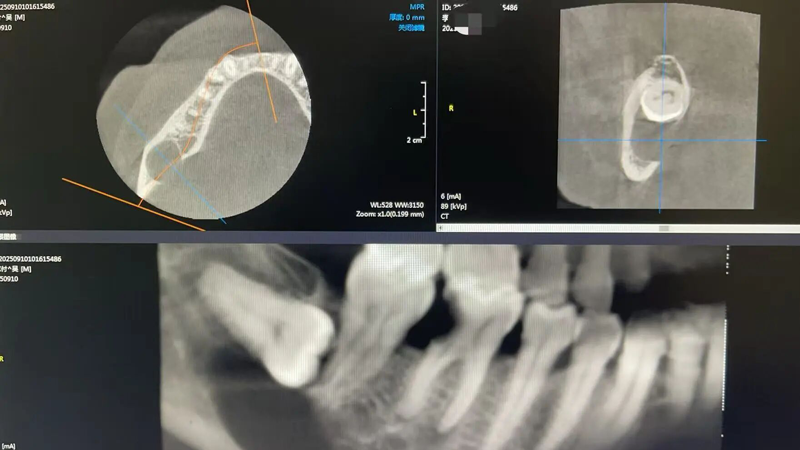

该患者主诉为“右下第一磨牙疼痛”,且年事已高,作为高龄患者并伴有高血压,拔牙会带来更多的风险,如出血与止血困难、心血管意外等。经口腔科详细检查及影像学显示,其“右下第三磨牙”为低位埋伏倒置阻生,伴随囊肿形成,且囊肿紧邻神经管,病情复杂,手术风险较大。

为确保手术安全,来凤县人民医院迅速启动技术协作机制。在我院坐诊的武汉大学口腔外科任建岗教授与口腔科主任张福全面评估患者CBCT影像与全身健康状况后,一致认为可实施局部麻醉手术。